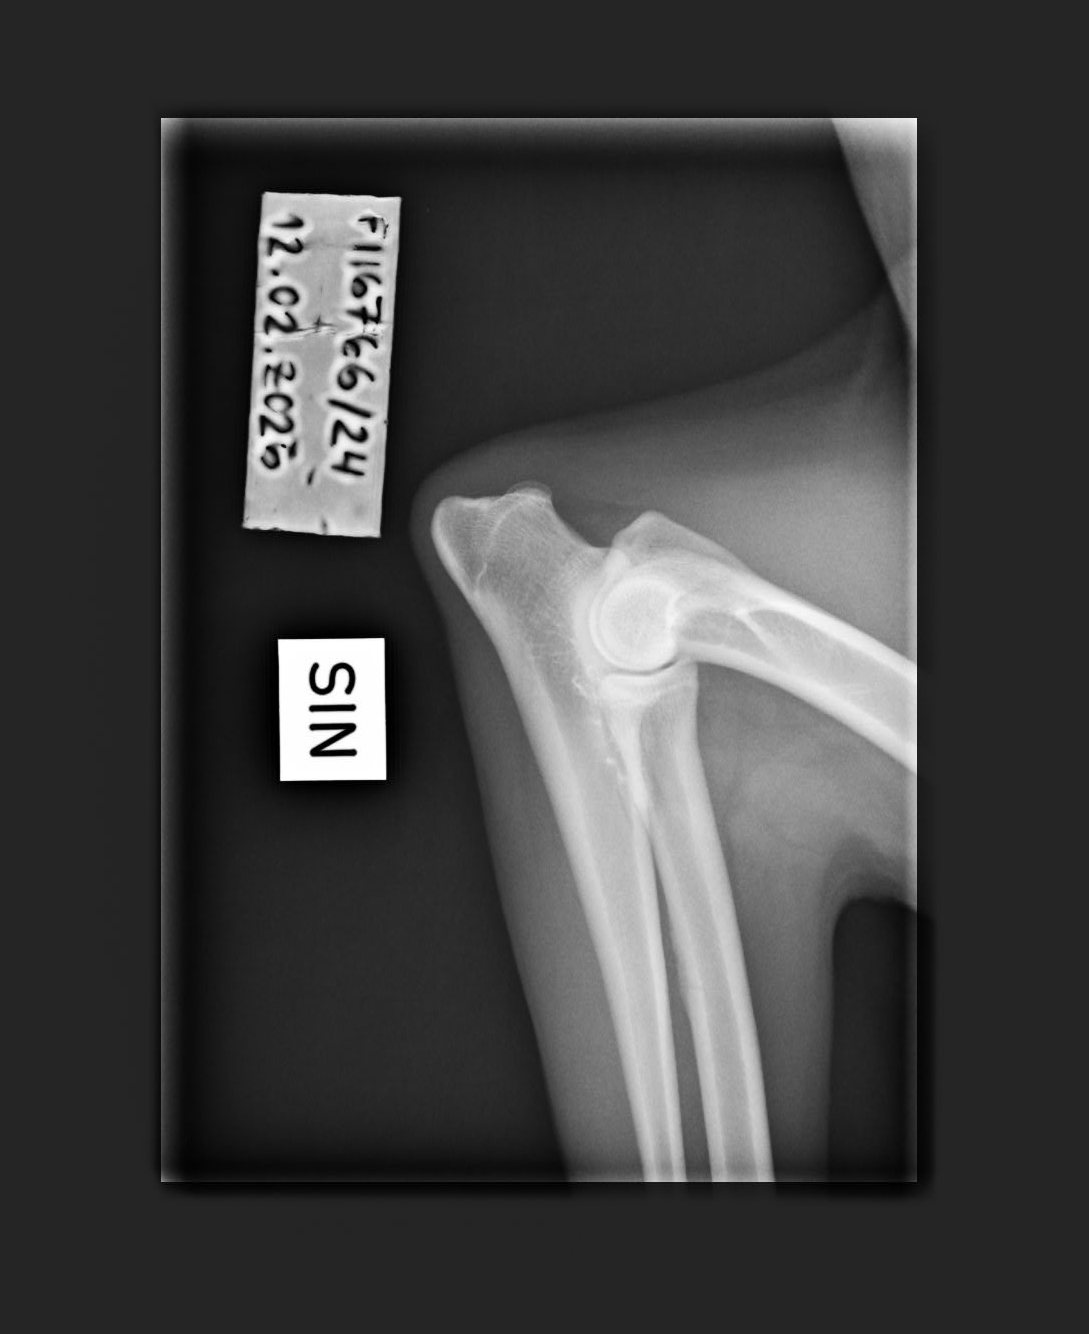

- Finnish Kennel Club's elbow x-ray report Dec '25: Signs suggestive of medial coronoid disease; further information about the condition of the joints can be obtained, if necessary, by computed tomography (CT) examination

- Finnish Kennel Club's elbow CT report Feb '26: A small amount of new bone formation around the medial coronoid process of the left elbow